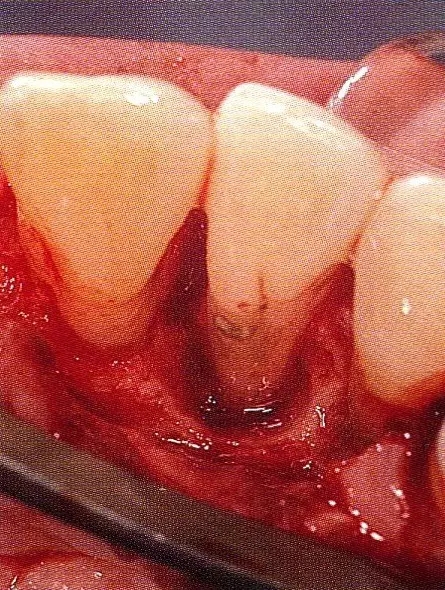

▲圖7-2  術(shù)前x片。確認(rèn)存在垂直性深骨缺損。